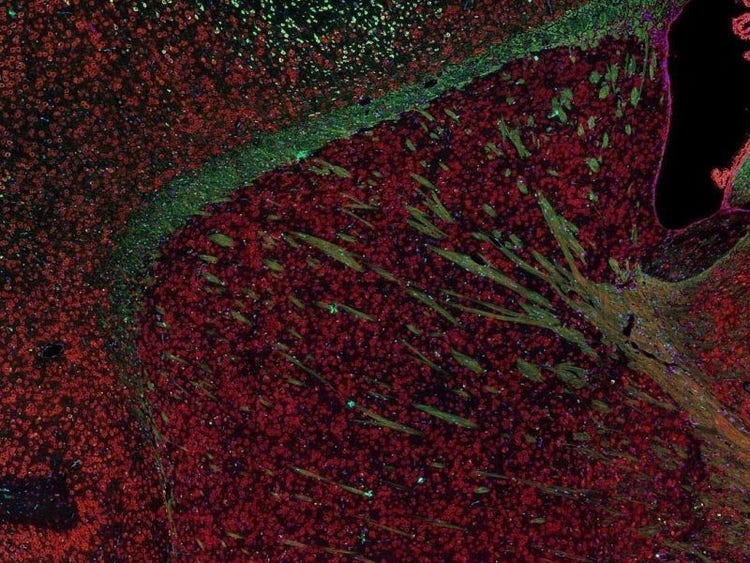

Fluorescence imaging of a mouse brain

각 확대 이미지는 특이해 보이지만, 모두 모아보면 형광 이미징으로 촬영한 생쥐 뇌가 나타납니다.

영국 과학자 George G. Stokes 경은 형석에 자외선을 비추면 형광을 발한다는 사실을 처음으로 목격했고, ‘형광’이라는 단어를 만들어냈습니다. Stokes 경은 형광 광원이 여기광원보다 파장이 더 길다는 사실을 발견했으며, 이 현상은 현재 스토크스 이동으로 알려져 있습니다. 형광 현미경은 자연적인 형태(일차 형광 또는 자가형광)이거나 형광을 발할 수 있는 화학물질로 처리했을 때 형광(이차 형광)을 발할 수 있는 물질을 연구하는 탁월한 방법입니다.